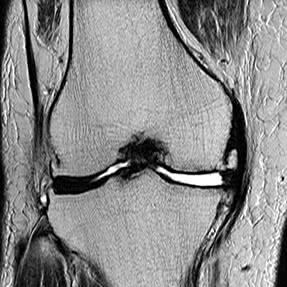

- MRI画像より、変形性ひざ関節症グレード4(末期)と診断。

-

大腿骨内側に突発性骨壊死があり、半月板も外周へ逸脱

膝蓋大腿関節に水がたまっているのが白く確認できる